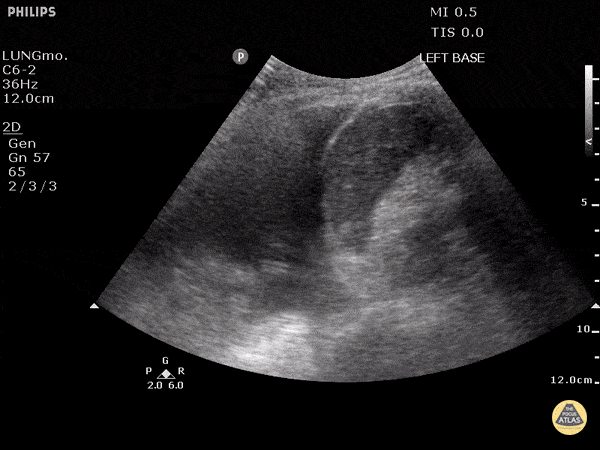

Pulmonary - Large Pleural Effusion

The left lung can be seen freely floating in anechoic fluid on the left side of the screen. Also pictured, the diaphragm, spleen, and edge of the beating heart. Justin Bowra MBBS, FACEM, CCPU Emergency Physician, RNSH et al.